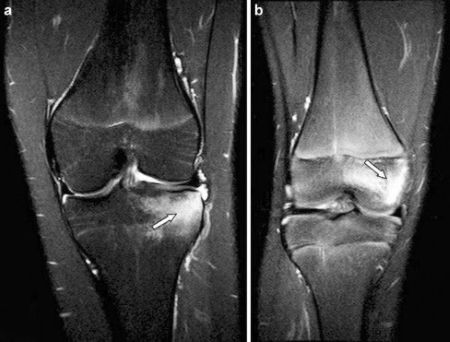

- MRI: The gold standard for visualizing soft tissues. Confirms ligament tears (partial or complete), meniscus tears (type and location), cartilage damage, and bone bruising (bone marrow edema).

Bone marrow edema (BME) seen on MRI is fluid accumulation within the bone, often indicating microfractures (bone bruise) associated with acute trauma (ligament tears, impaction) or sometimes related to osteoarthritis or stress reactions [3]. Its presence can correlate with pain severity and associated structural damage.